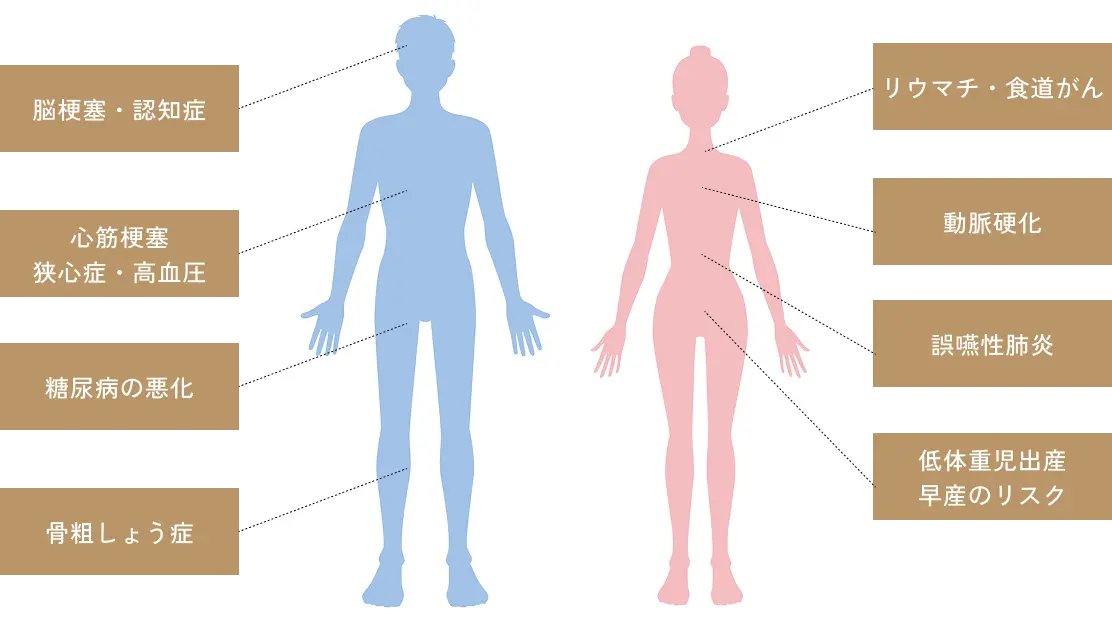

歯周病と全身疾患の関係

口腔内の健康は

全身の健康に繋がります

歯ぐきなど歯周組織の炎症が生じる歯周病では、歯周病菌の毒素が血管から全身を巡ってしまうことがあります。このことは、心筋梗塞、狭心症、誤嚥性肺炎、動脈硬化など様々な全身疾患のリスクに繋がります。身体の健康を守るためにも、まずは口腔内のケアや歯周病などの歯科疾患の早期発見・治療に努めましょう。